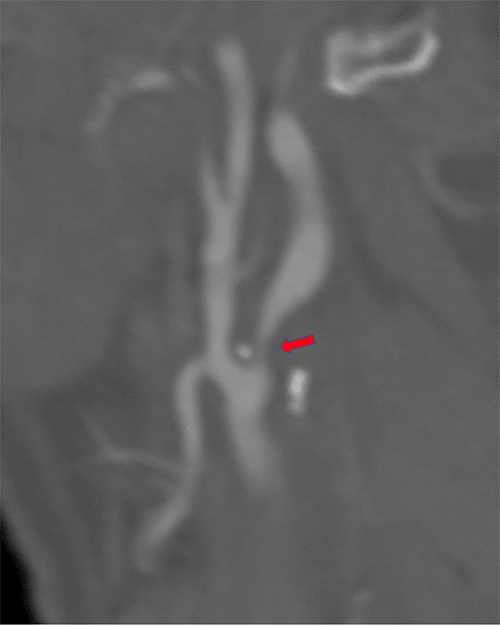

After recovering from his left TCAR and being seen in follow-up, he then underwent an elective right TCAR. Right carotid angiogram demonstrated severe focal ICA stenosis consistent with preoperative imaging (Figure 3A). Angioplasty was performed with a 5 × 20 mm balloon, followed by deployment of a 9 × 30 mm ENROUTE Transcarotid Stent (Silk Road Medical, Sunnyvale, CA). The completion angiogram demonstrated a satisfactory result (Figure 3B). He was hemodynamically stable and discharged home on postoperative day 2 without new neurologic symptoms. The patient was discharged on dual antiplatelet therapy with aspirin 81 mg once daily and clopidogrel bisulfate 75 mg once per day.

Figure 3. Right Carotid Angiogram During TCAR Procedure Before A) and After B) Angioplasty and Stent Deployment. Published with Permission

A.

B.